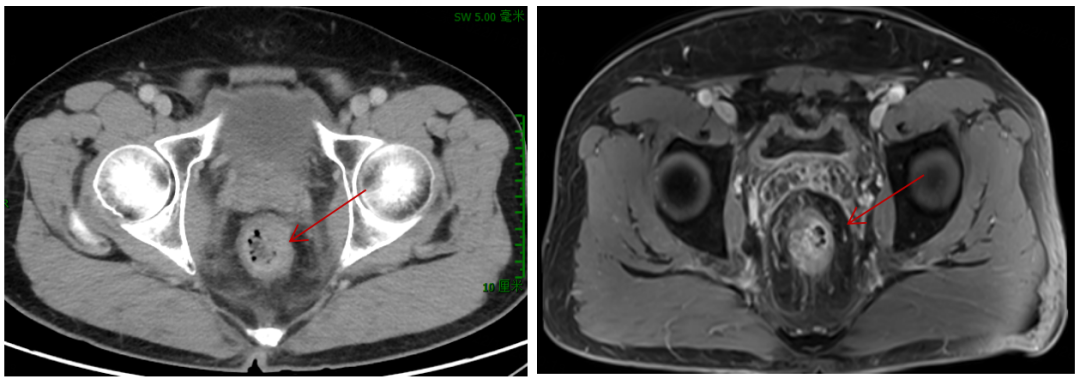

2021年5月13日开始每3个月复查1次,疗效评估均为持续PR。

图7 盆腔CT